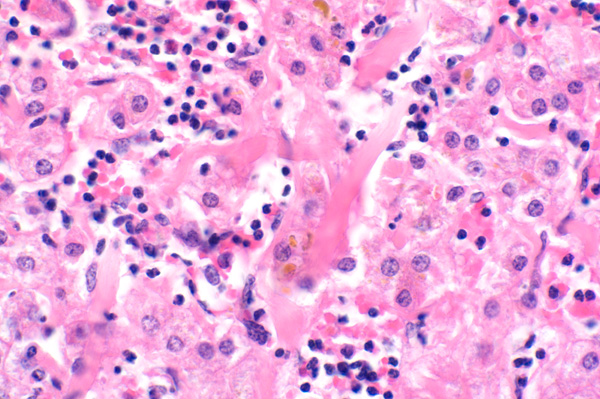

Subendothelial collagen (fibrosis) (*) expands sinusoids and disrupts hepatic cords architecture. Surrounding hepatocytes are swollen with vacuolated cytoplasm (degeneration), or shrunken with cytoplasmic hypereosinophilia and pyknotic nuclei (necrosis).